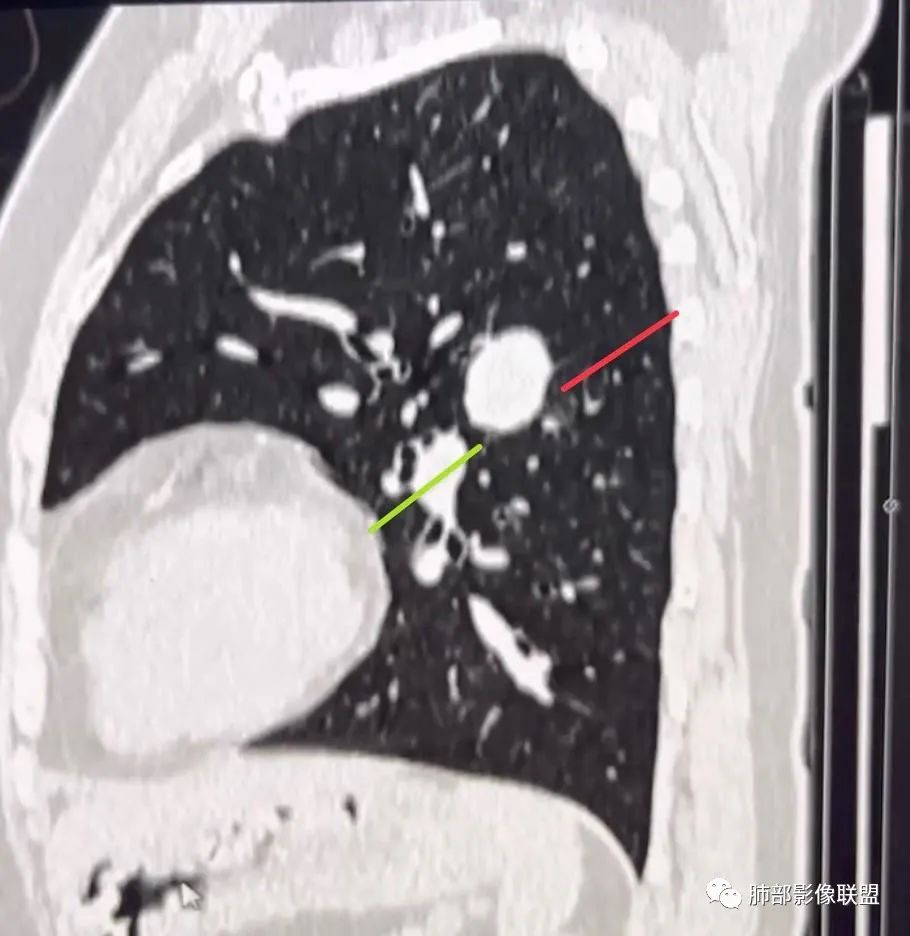

视频连续观察,红色标记部分确定是叶间裂,按照这个叶间裂走行的推测,过了病灶以后,叶间裂大概是绿色箭头的样子

曹冠杰

但是,绿色箭头部分的叶间胸膜找不到了。再通过完整的矢状位视频反复观看,这个叶间裂的发育确实是有问题的,中间有断层。

已显示的这部分胸膜,无论是从轴位还是冠状位还是矢状位,走行或形态丝毫不受影响,叶间裂与病灶交界区甚至看不到丝毫的异常。更别说胸膜尾征象。

这个叶间裂发育不全的证据,无胸膜尾,再加上病灶的:血管推移、强化方式、钙化、肺气肿等征象也会优先倾向于 PSP。我觉得这就已经形成了优先诊断 PSP,而不是胸膜来源病变的完整的自圆其说证据链了。

如果看不到这个证据,思维逻辑是这样的:我优先诊断 PSP,然后确实跨裂了,然后用叶间裂发育不全去解释。

前者是诊断倾向性的依据。后者是站在结果的基础上的推测。不一样的。你琢磨琢磨这个味道。

这个病灶很特殊。特殊就在于他是PSP,而且还靠近肺门区,还和叶间胸膜连着,还确实能看到叶间裂发育有问题。真是很有意思的病例,真的很容易诊断为胸膜来源病变。如果是其他炎性病变,让我们找到了支气管进入的证据,我们也早就一锤定音定位肺内了。